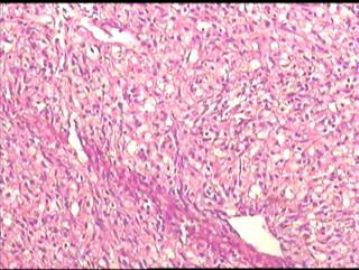

•25岁,女性,停经35周,发现腹腔包块1月余。

•手术所见:右侧卵巢肿瘤,12×8.6×8.0cm大小,表面光滑,内实质似鱼肉样、部分区域胶冻状,伴少许盆腔积水。

• 卵巢肿瘤图4

图4

性索间质来源的肿瘤。

硬化性间质瘤